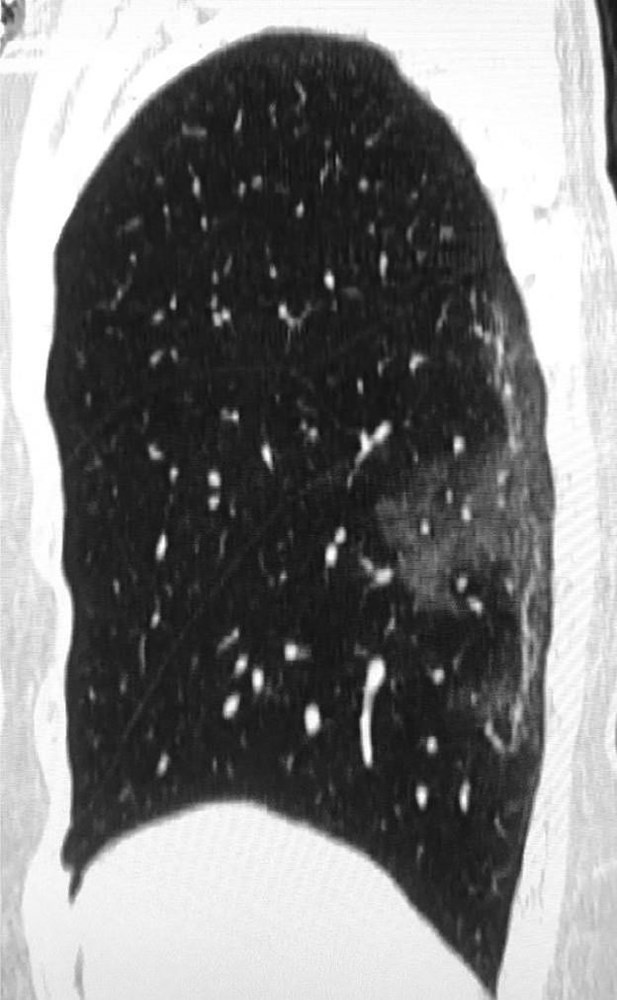

Akciğerlerde meydana gelen farklı koşullar yani kan damarı anormallikleri ve romatoid artrit tarzındaki sorunlar akciğerde leke meydana getirir. Akciğerde leke oluşumu bilindiğinden daha yaygın görülen bir sorundur. Sıvı akciğerlerdeki nefes almamızı sağlayan küçük keselere alveollere sızar. Kanserli hücrelerin akciğer zarında birleşip tümör oluşturması da akciğer lekelenmesinin en tehlikeli boyutudur.

Akciğerde oluşabilecek her türlü hastalıkta sigara ilk sıralarda yer alan etken maddedir. Fakat akciğerde leke oluşumu kanser veya mantar gibi diğer sorunların belirtisi olarak da ortaya çıkabilir ve zaman kaybetmeden tedavi edilmelidir. Bazı vakalarda bezelye yetiştiği görülürken bazılarında direkt olarak köknar ağacı gibi bitkilerin filizlendiği görülmüştür. Tüberküloz hastalığı akciğer kalınlaşmasında ilk akla gelen nedenlerden bir tanesidir.

corona virusun bulastigi hastanin 3d akciger goruntusu yayinlandi iste akcigerlere verdigi hasar video